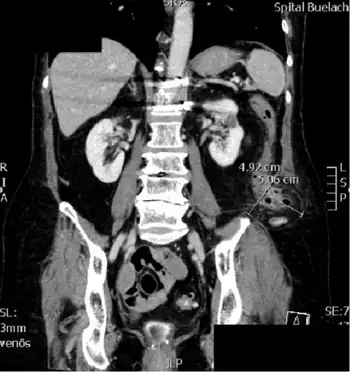

Petit's hernia is a hernia that protrudes through the lumbar triangle (aka Petit's triangle).[1] This triangle lies in the posterolateral abdominal wall and is bounded anteriorly by the free margin of external oblique muscle, posteriorly by the latissimus dorsi and inferiorly by the iliac crest. The neck (the spot where the hernia protrudes into the opening) is large, and therefore this hernia has a lower risk of strangulating than some other hernias.